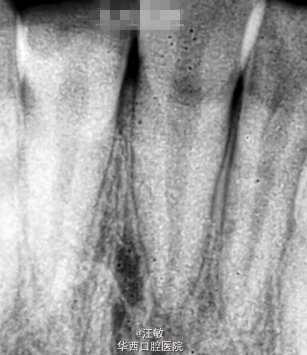

患者男,12岁,21牙外伤折断露髓,进行根管治疗后用树脂材料直接将碎片与剩余牙体组织粘接。 此方法虽能够最大限度的保留牙体组织,但也存在一定局限性,例如牙体变色,碎片再脱落,不能承受过大咬合负荷。